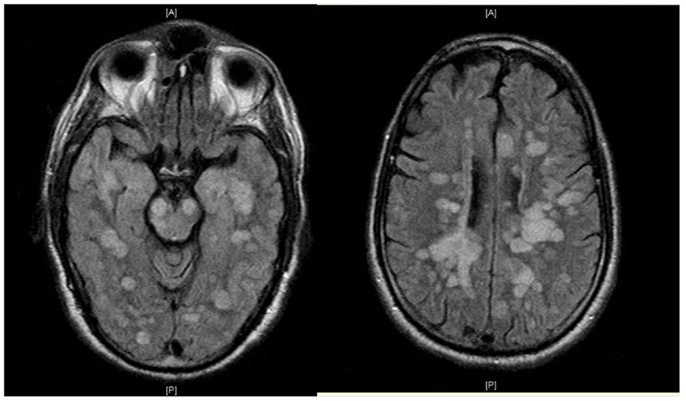

Демиелинизирующие заболевания мозга: МРТ изображения